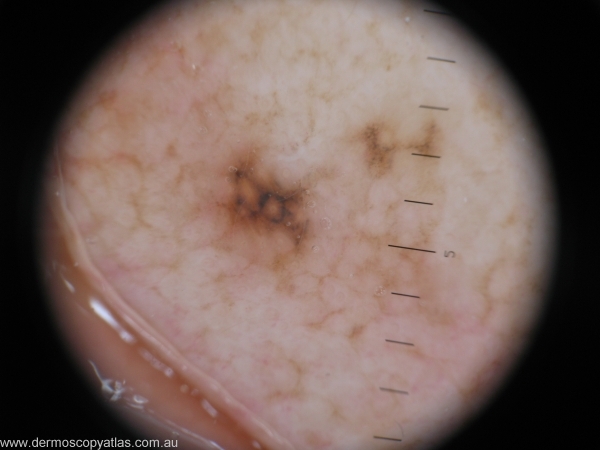

Case 3 42 year old Golf course curator. Left pinna lesion noted on routine skin check. Patient unaware of lesion.

Question: What is your provisional diagnosis? Consider Atypical spitz, Pigmented IEC, Lentigo maligna, Solar lentigo and Compound nevus with regression.